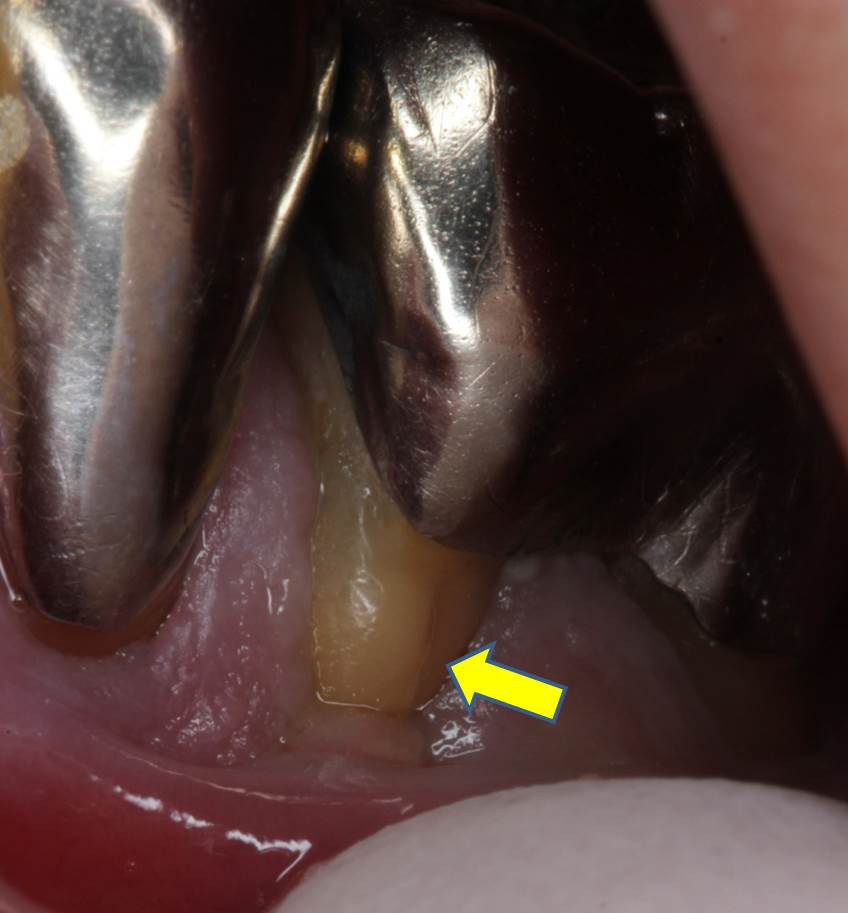

検診でむし歯が見つかるケースが増えてきていますが、銀歯の中が齲蝕になっていることに多くの歯医者は気付くことがありません。お口の奥には光源が無く、銀歯は黒い金属であるため、暗い光しか反射せず、銀歯の縁がいかに黒くなろうとも歯科医師の目に届かないことも多いようです。画像は、銀歯の縁から虫歯になっており、矢印部分はクラック(ひび割れ)が見られた患者様の大臼歯の写真です。神経も取り除いている歯であるようなので痛みは出ないと思われますので、早期に介入する必要があります